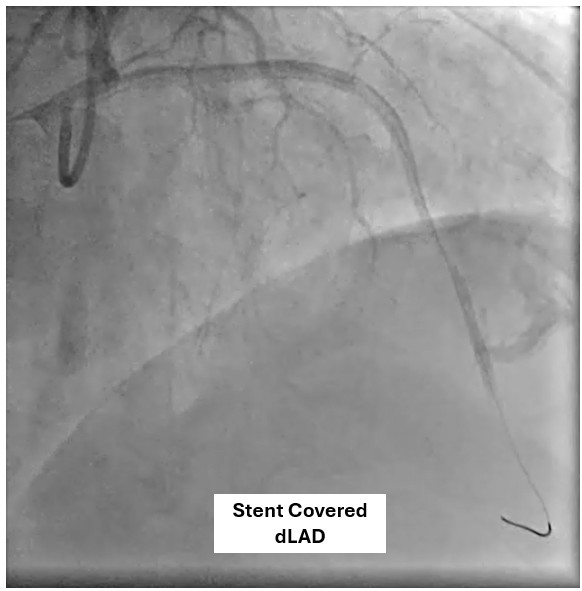

The patient underwent coronary angiography, where the team attempted to reopen the previously stented proximal mid LAD that had become occluded. After multiple revascularization efforts from ballooning to placing a ne DES in the mid LAD. A type III perforation occurred in the distal LAD during balloon inflation. Despite immediate measures including balloon tamponade and covered stent deployment, the perforation remained visible on follow-up angiography.

A covered stent was deployed in the distal LAD in an attempt to seal the coronary perforation; however, angiography showed that the Type III perforation persisted despite the intervention. Additional balloon inflation within the stent was performed, but the leakage could not be completely sealed. The patient remained hemodynamically stable without signs of cardiac tamponade or pericardial effusion. The following day, repeat coronary angiography was conducted to reassess the condition, which confirmed persistent contrast extravasation from the LAD into the left ventricular cavity, indicating the formation of a coronary–ventricular fistula. Given the hemodynamic significance and the risk of progressive left ventricular dysfunction due to continuous shunting, a multidisciplinary decision was made to proceed with surgical correction. The patient subsequently underwent successful LAD–LV fistula patch repair combined with. Surgical repair remains the definitive management for such cases, and early recognition with timely intervention is crucial to restore cardiac function and prevent irreversible myocardial damage.